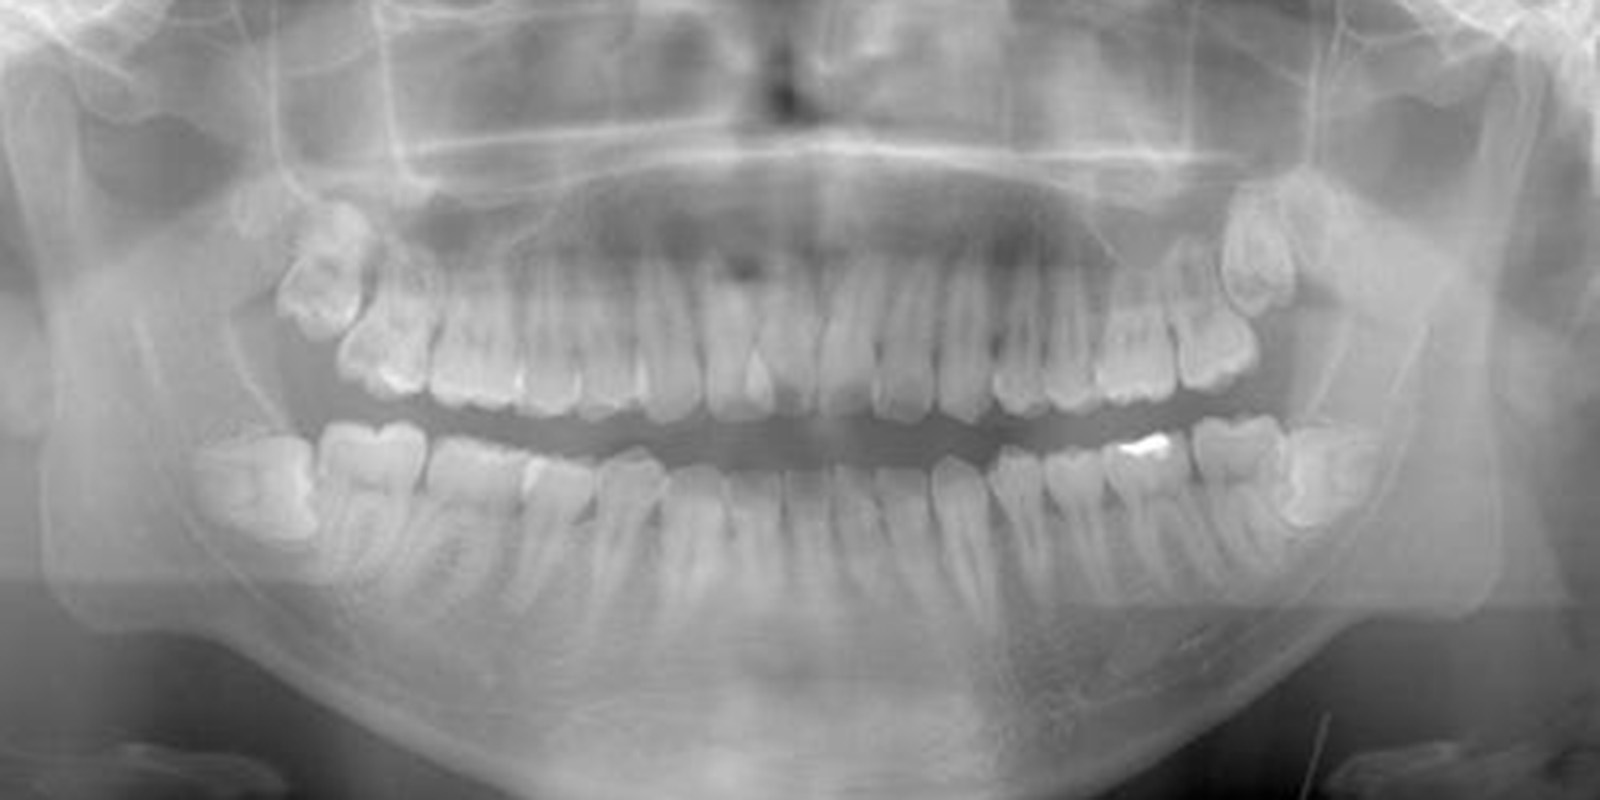

親知らずがあるレントゲン画像

基本的には、どのようなケースでも

対応します

ただ根の先に下顎管が触れているようなケースであれば2回で対応したりしますが歯の頭の部分が下顎管と触れているような稀なケース、親知らず周りが嚢胞になってしまっているケース、全身疾患がある方、外科処置が困難な方に関しては大学病院を紹介させていただくこともあります。

1. レントゲン、口腔内検査によって抜歯の可否を決める。